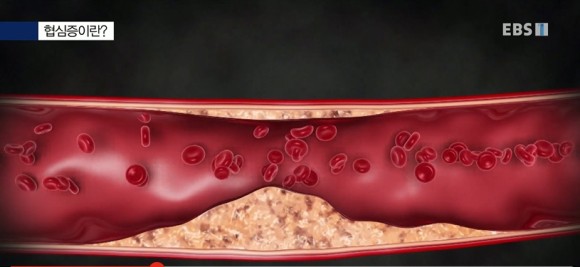

고지혈증이란 Q. 고지혈증을 방치할 경우 어떤 질환으로 이어집니까?직접적으로 영향을 받는 것은 혈관입니다. 시간이 지나면서 서서히 혈관이 좁아지면서 마침내 막히게 되고, 고지혈증과 흡연, 당뇨병, 고혈압이 동반되면 혈관 스트레스가 최대로 높아져 혈관벽이 약해지고 갈라져 파열되므로 혈병(혈전)이 생기게 되는 것입니다.

EBS 이름 협심증 환자 사례 협심증이란 오랜 세월 콜레스테롤 같은 지방 찌꺼기가 심혈관에 축적돼 혈관이 좁아지고 흉통이 나타나는 증상입니다. 그로 인해 심장에 들어가는 혈액의 양이 줄어들고 심장 기능에도 이상이 생깁니다.

LDL: 간에서 만든 콜레스테롤을 쌓아 혈액을 따라 조직으로 옮기는데 이때 혈액 속에 콜레스테롤이 너무 많으면 혈관 벽에 스며들어 혈관이 좁아지는 동맥경화가 나타나게 됩니다.